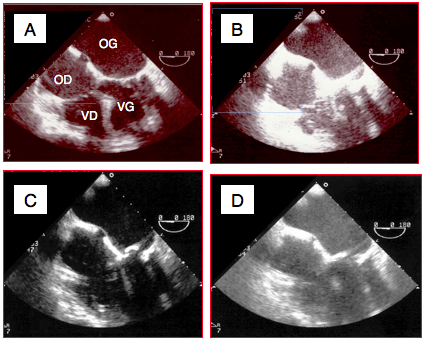

Figure 25.9 : Effets du gain et de la compression sur le rendu d'une même image à l'écran (vue 4-cavités 0°). A: gain et compression normaux. B: excès de gain; le contraste noir-blanc est violent, les structures fines ont disparu. C: faible compression; le contraste noir-blanc est accentué par manque de nuance dans les gris. D: excès de compression; le niveau des gris est trop élevé, le degré de contraste est trop faible pour distiguer des structures fines.